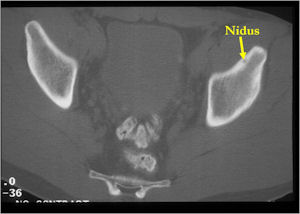

CT Scan:

- Well defined nidus with a smooth peripheral margin; +/- mineralization (CT more sensitive than XR and MRI for detecting mineralization); CT is better for detecting nidus in presence of exuberant sclerosis

- Radiographic Presentation